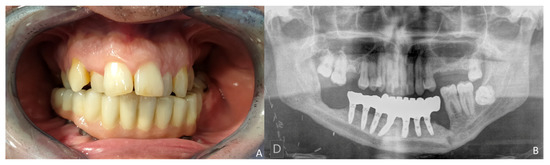

Six months later, the ossification of the graft and volume of the soft tissue were verified. An intraoral approach was performed, the titanium mesh was removed and the increase in height and width achieved with the graft was verified, showing the space beneath the titanium mesh completely filled with new hard tissue (Figure 8A). Seven dental implants were placed (Ticare®, Valladolid, Spain) (Figure 8B), and, four months later, the second surgical procedure of the implants was performed (Figure 9A). Evaluation of the occlusal vertical dimension and record centric relation was accomplished (Figure 9B) and the metal framework was evaluated intraorally (Figure 10A).

The prosthetic rehabilitation was carried out by means of a fixed implant-supported prosthesis providing normal occlusion (Figure 10B and Figure 11A). Three years later, there was no evidence of significant peri-implant bone resorption (Figure 11B). The prosthetic rehabilitation allowed a correct aesthetic and functional result with a regular diet and intelligible speech (Figure 12A,B).

Figure 11. Functional result. (A) Final dental restoration. (B) Panoramic radiograph demonstrating the reconstruction of the previous height of the mandible with a correct osseointegration of the implants.